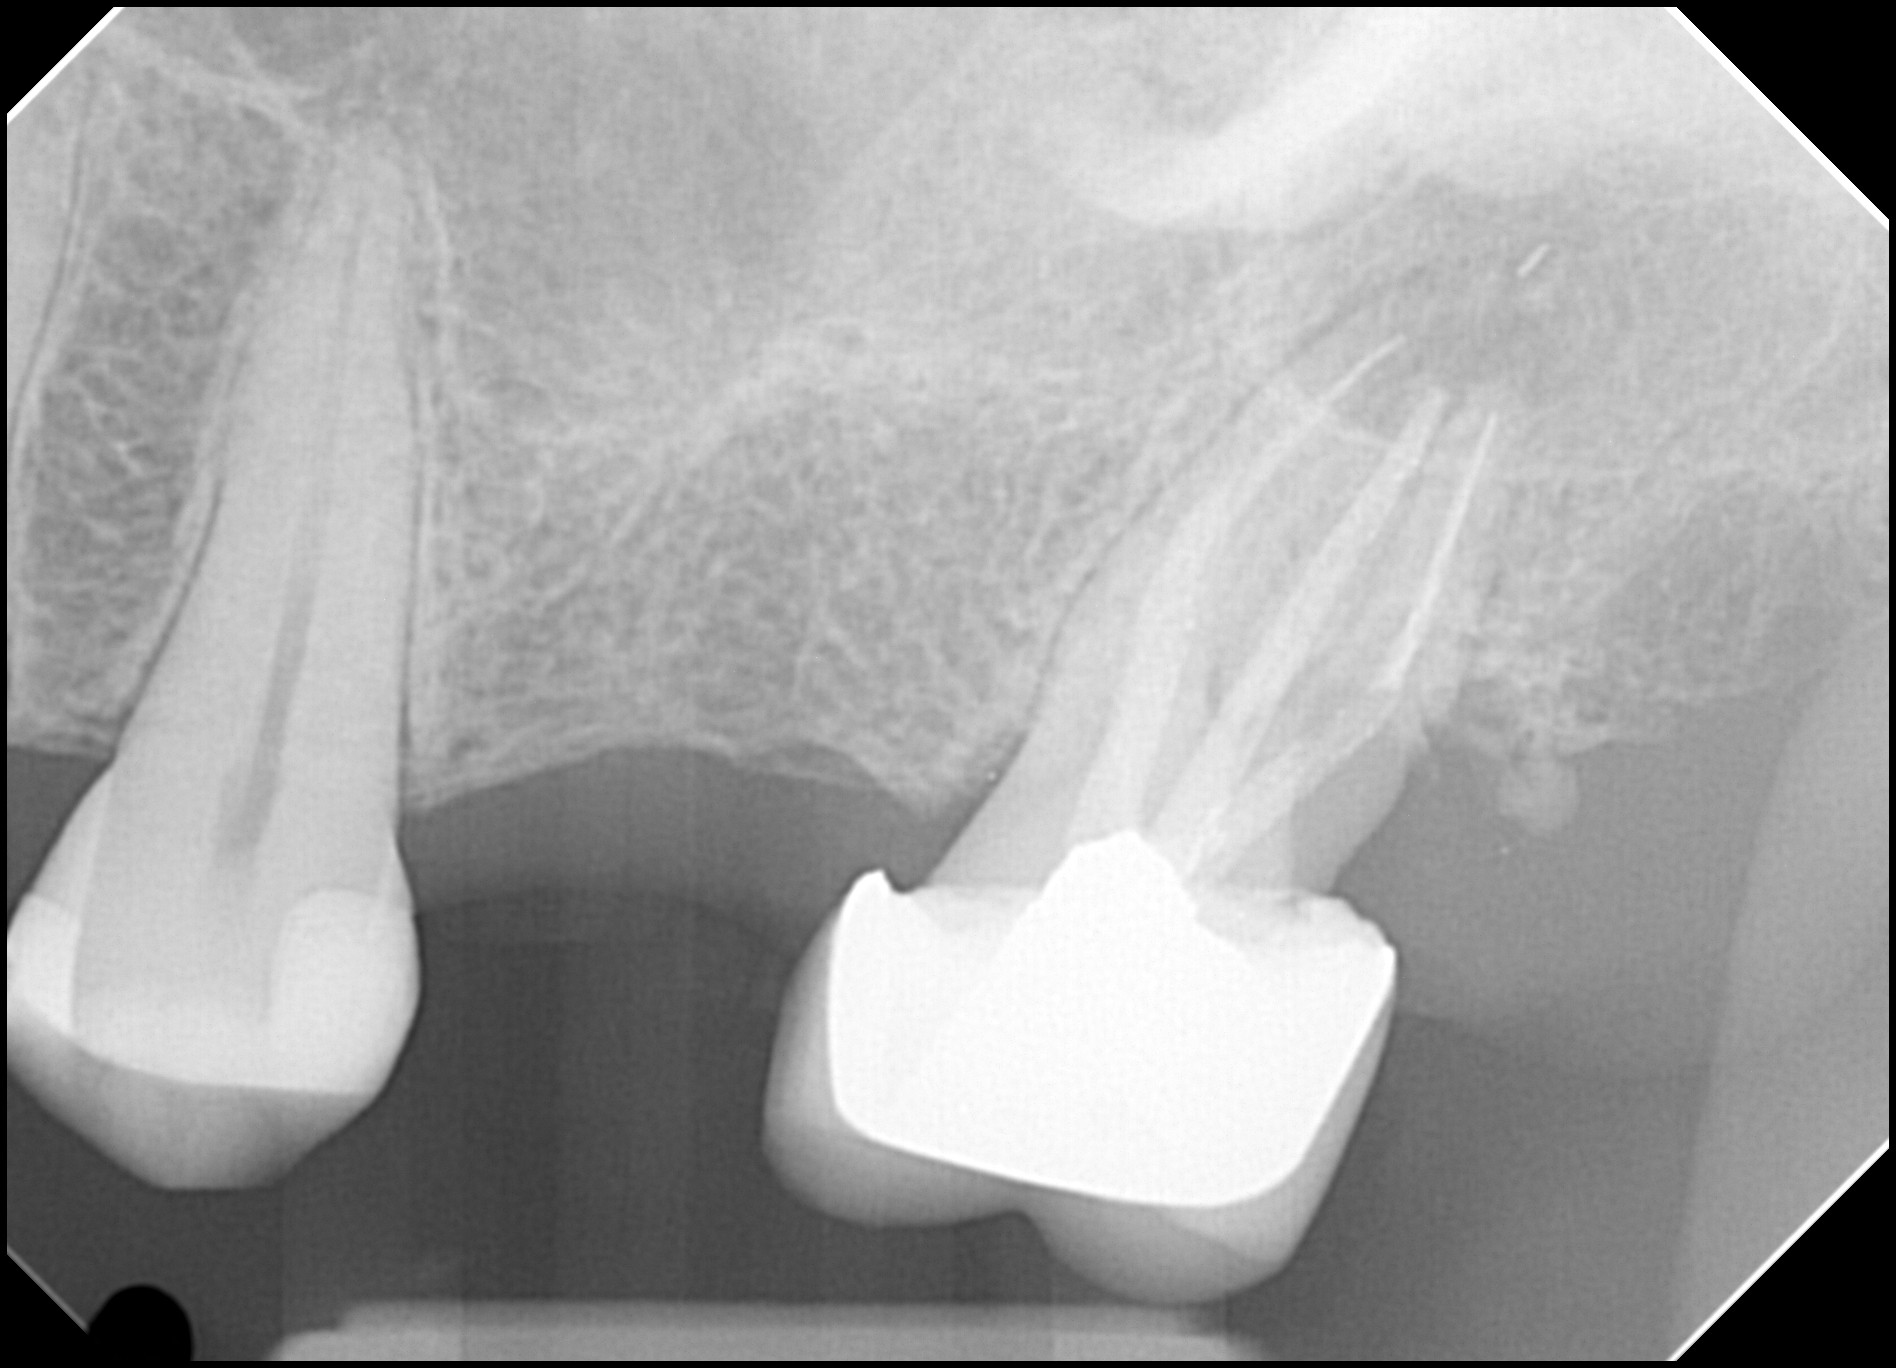

27. What option can be selected for the restoration on the upper jaw?